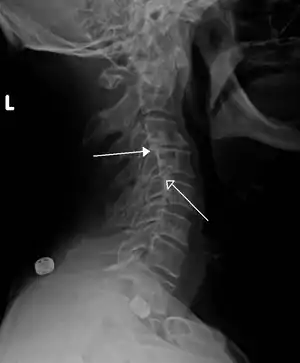

| Grade 1 retrolistheses of C3 on C4 and C4 on C5 | |

Since the vertebral body in a retrolisthesis moves in a posterior direction, the grading used for spondylolistheses is of little use. It is however useful to divide the anterior to posterior dimension of the intervertebral foramina (IVF) (4) into four equal units. A posterior displacement of up to ¼ of the IVF is graded as Grade 1, ¼ to ½ as Grade 2, ½ to ¾ as Grade 3, ¾ to total occlusion of the IVF as Grade 4. Alternatively, a measurement of the amount of displacement can also made by measuring the bone displacement in millimetres.